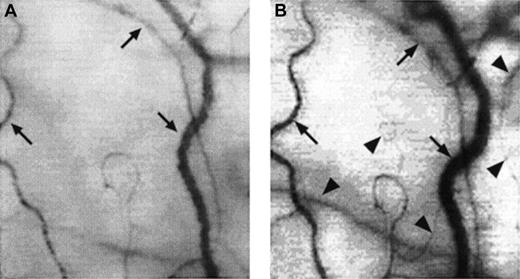

Two frame-captured images showing microvascular changes during crisis resolution in the same SCD patient.

Optical magnification, × 4.5; onscreen magnification, × 125. Focusing was aimed at the same location during crisis and crisis resolution, with the same vessel serving as its own reference baseline. (A) During crisis, there is significant reduction in vessel diameter and disappearance of capillaries and arterioles, resulting in extreme avascularity. The arrows point at the three vessels targeted for longitudinal comparison during crisis resolution. (B) An increase in vessel diameter and reappearance of capillaries and arterioles occur during crisis resolution. The vessels indicated by the arrows show a significant increase in vessel diameter. In addition, capillaries and arterioles (arrowheads) reappear during crisis resolution.

There was a significant decrease in conjunctival vascularity during painful crisis, with a close to complete absence of capillaries and a significantly reduced presence of arterioles and small venules from the steady-state conditions (Figures3 and4A). In most cases, the disappearance of capillaries and small arterioles arose as a result of the absence of blood flow into these microvessels.

A few of the sludged large vessels did not show much change in diameter during crisis; however, most of the remaining large vessels showed an averaged decrease of 36.7% ± 5.2% in the diameter (compare Figures4A and 4B).

These acute microvascular abnormalities were transient, and the microvasculature reverted to steady-state values after resolution of painful crisis (postcrisis). In reality, normal steady-state values are comparable to postcrisis values made 1 month after crisis resolution. During crisis resolution, reemergence of capillaries and arterioles (reperfusion) was observed in all patients (Figure 4B).